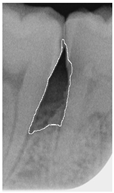

Table 14. Periodontal image validation with 5-fold CNN validation.

Ground Truth

Angle < 37

Bioengineering 12 00043 i001Bioengineering 12 00043 i002Bioengineering 12 00043 i003Bioengineering 12 00043 i004

Accuracy94.80% angle < 3797.53% angle < 3798.13% angle < 3797.65% angle < 37

Angle > 37

Bioengineering 12 00043 i005Bioengineering 12 00043 i006Bioengineering 12 00043 i007Bioengineering 12 00043 i008

Accuracy96.19% angle > 3796.30% angle > 3799.36% angle > 3798.37% angle > 37